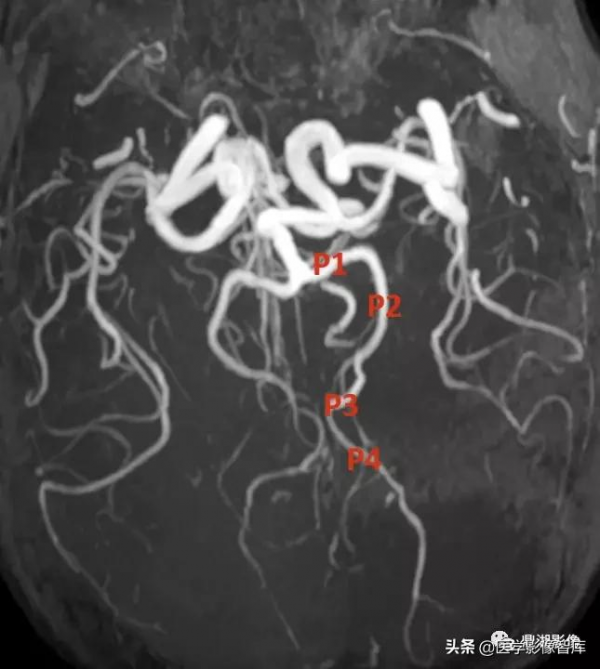

大腦後動脈(PCA)

1. 基底動脈

2. 後交通動脈

3. PCA P1 段

4. 穿支

5. P2 段

6. 小腦上動脈

7. 基底動脈的腦橋支

8. 顳前動脈

9. 顳後動脈

PCA 分 4 段:P1 交通前段;P2 環池段;P3 四疊體段;P4 距裂段

PCA 分出 3 種類型分支:中央支、腦室及脈絡叢支及大腦支。